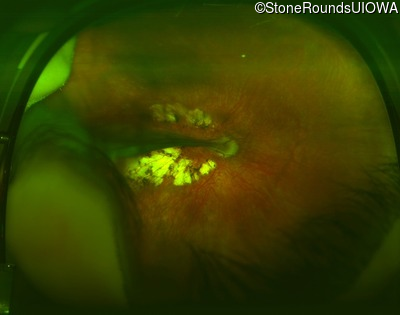

AD Familial Exudative Vitreoretinopathy (IIIE2b)

Age at visit: 23 months

This 23 month old male has had nystagmus since shortly after birth. He was born at term (7lbs 12oz).